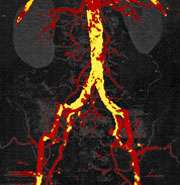

dual energy post bone plaque removal

CT angiogram post automated bone and plaque removal clearly visualizes stenotic arterial segments.